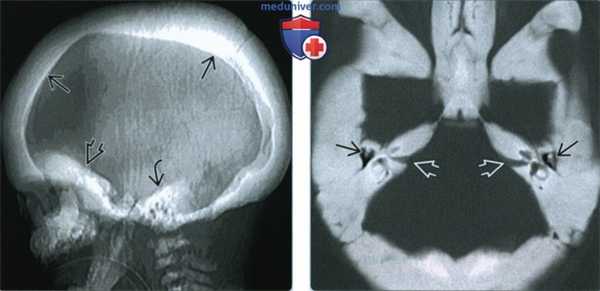

(Слева) Рентгенография в боковой проекции: определяется значительное поражение черепа, наблюдаемое при младенческом (аутомосно-рецессивном) остеопетрозе. Обратите внимание на выраженный гиперостоз основания черепа.

(Справа) Рентгенография черепа в боковой проекции: определяется менее выраженный остеопетроз. В этом случае основание черепа не поражено. Основание черепа однако плотное и гиперостозное. Такой характер поражения наиболее часто наблюдается у взрослых при заболевании II типа. (Слева) КТ, костное окно, сагиттальный срез: выраженное утолщение кости с поражением основания и свода черепа. Обратите внимание, насколько толстым стал скат черепа. Череп и тела позвонков имеют крайне высокую плотность. Обратите внимание на щажение верхней челюсти.

(Справа) КТ, косное окно, аксиальный срез: у пациента с аутосомно-рецессивным остеопетрозом определяется плотное склерозирование и утолщение височной кости и основания черепа. Гиперостоз может привести к поражению и сужению внутреннего слухового канала. (Слева) КТ, костное окно, аксиальный срез: определяется выраженный гиперостоз и склероз при остеопетрозе. Костномозговые пространства полностью облитерированы. Наружные слуховые каналы полностью окклюзированы, среднее ухо сужено с двух сторон. Эти изменения привели к развитию глухоты.

(Справа) MPT Т2ВИ, сагиттальный срез: картина в виде черной кости, наблюдаемая при остеопетрозе. Такая картина обусловлена полным замещением костно-мозгового пространства плотной костной тканью. Нарушение функции костного мозга - причина смерти при младенческой форме этого заболевания.

(Слева) При рентгенографии в боковой проекции определяется диффузное утолщение свода черепа, основания черепа и височной кости, что характерно для более тяжелой формы остеопетроза (аутосомно-рецессивной).

(Справа) При КТ костей основания черепа в аксиальной проекции наблюдается диффузный склероз всего основания черепа. Отмечается сужение полости среднего уха с обеих сторон. Также обратите внимание на поражение обоих внутренних слуховых проходов. У этого ребенка был диагностирован аутосомно-рецессивный остеопетроз. (Слева) При аксиальной КТ в костном окне основания черепа у молодого человека с аутосомно-доминантным остеопетрозом 2 типа наблюдается двусторонний плотный склероз височных костей и утолщение свода черепа, однако повышения плотности костей не отмечено. Обратите внимание на изменения обоих скуловых бугров типа «кости в кости» - остатки нерезервированных центров оссификации.

(Справа) При аксиальной КТ в костном окне у этот же пациента с остеопетрозом в проекции левой височной кости наблюдается протрузия патологической ткани пораженной кости внутреннего уха во внутренний слуховой канал.

(Справа) При КТ костей основания черепа в аксиальной проекции наблюдается диффузный склероз всего основания черепа. Отмечается сужение полости среднего уха с обеих сторон. Также обратите внимание на поражение обоих внутренних слуховых проходов. У этого ребенка был диагностирован аутосомно-рецессивный остеопетроз.